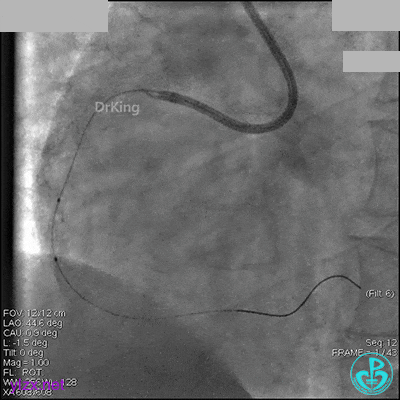

冠脉造影

入院次日冠脉造影显示粗大左主干末端中度狭窄,前降支开口严重狭窄,回旋支与前降支角度大,弥漫性长病变,严重狭窄,粗大右冠脉近中段弥漫性中重度狭窄。由于病变复杂,造影结束后先下台,择期再行介入治疗。

AL 1.0指引导管到位,简单短时尝试导丝不能顺利通过前降支或回旋支病变。改变策略处理右冠脉病变,计划植入2枚支架。AL指引导管到位,Sion blue导丝到达右冠脉远端。导丝通过后1.5mm及2.5mm球囊14~16atm充分扩张中段病变。

右冠脉中段充分扩张后欲植入3.5×38mm支架时,支架难以通过中远段扭曲处,且指引导管、导丝弹出飞扬。反复尝试导丝重新到达右冠脉远端时通过不顺利,局部造影剂滞留,远端血流接近3级。